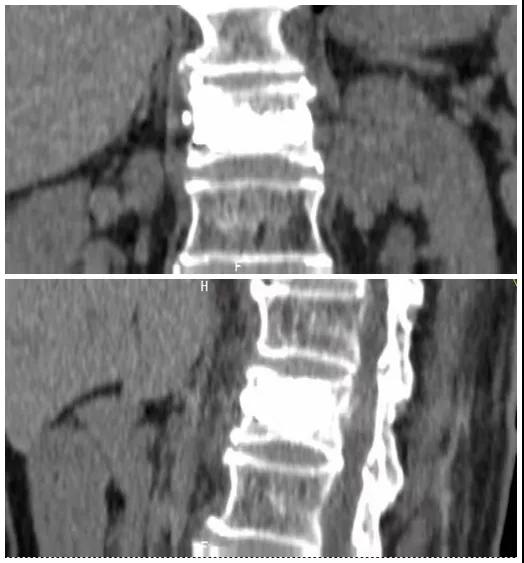

術(shù)前磁共振檢查提示腰1椎體新鮮壓縮性骨折

術(shù)后復查CT可見骨水泥彌散充分